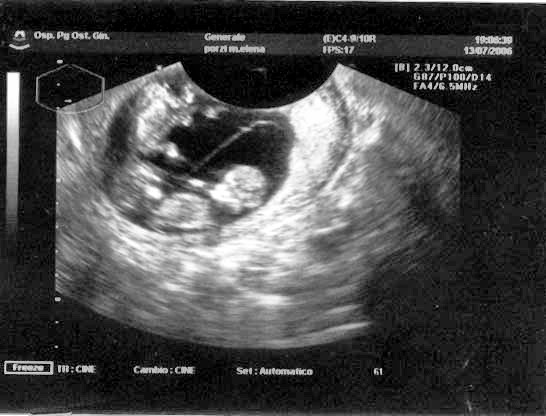

Qual è il costo dell’ecografia morfologica, in gravidanza? E che cos’è? Si tratta di un esame eseguito nel secondo trimestre ed è una delle tre eco obbligatorie.

E’ così chiamata perché studia la morfologia del feto al fine di escludere o accertare patologie. Nello specifico: la morfologica serve per valutare le dimensioni del feto, la struttura della placenta, la quantità di liquido amniotico, il collo dell’utero e serve inoltre ad indicare se il piccolo si sta formando normalmente o se sono state riscontrate delle alterazioni.